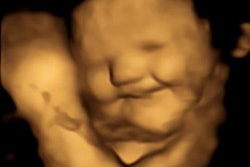

There are few things in radiology more amazing than 4D ultrasound, especially when used for fetal imaging. And in a new study in our Ultrasound Community, researchers from the U.K. found a novel use for the technology -- analyzing in utero how fetuses respond to taste and smell.

The researchers gave pregnant women capsules containing strong flavors, then used 4D ultrasound to view reactions of the fetuses a short time later. We could try to describe their reactions, but this is a classic case of a picture being worth a thousand words.